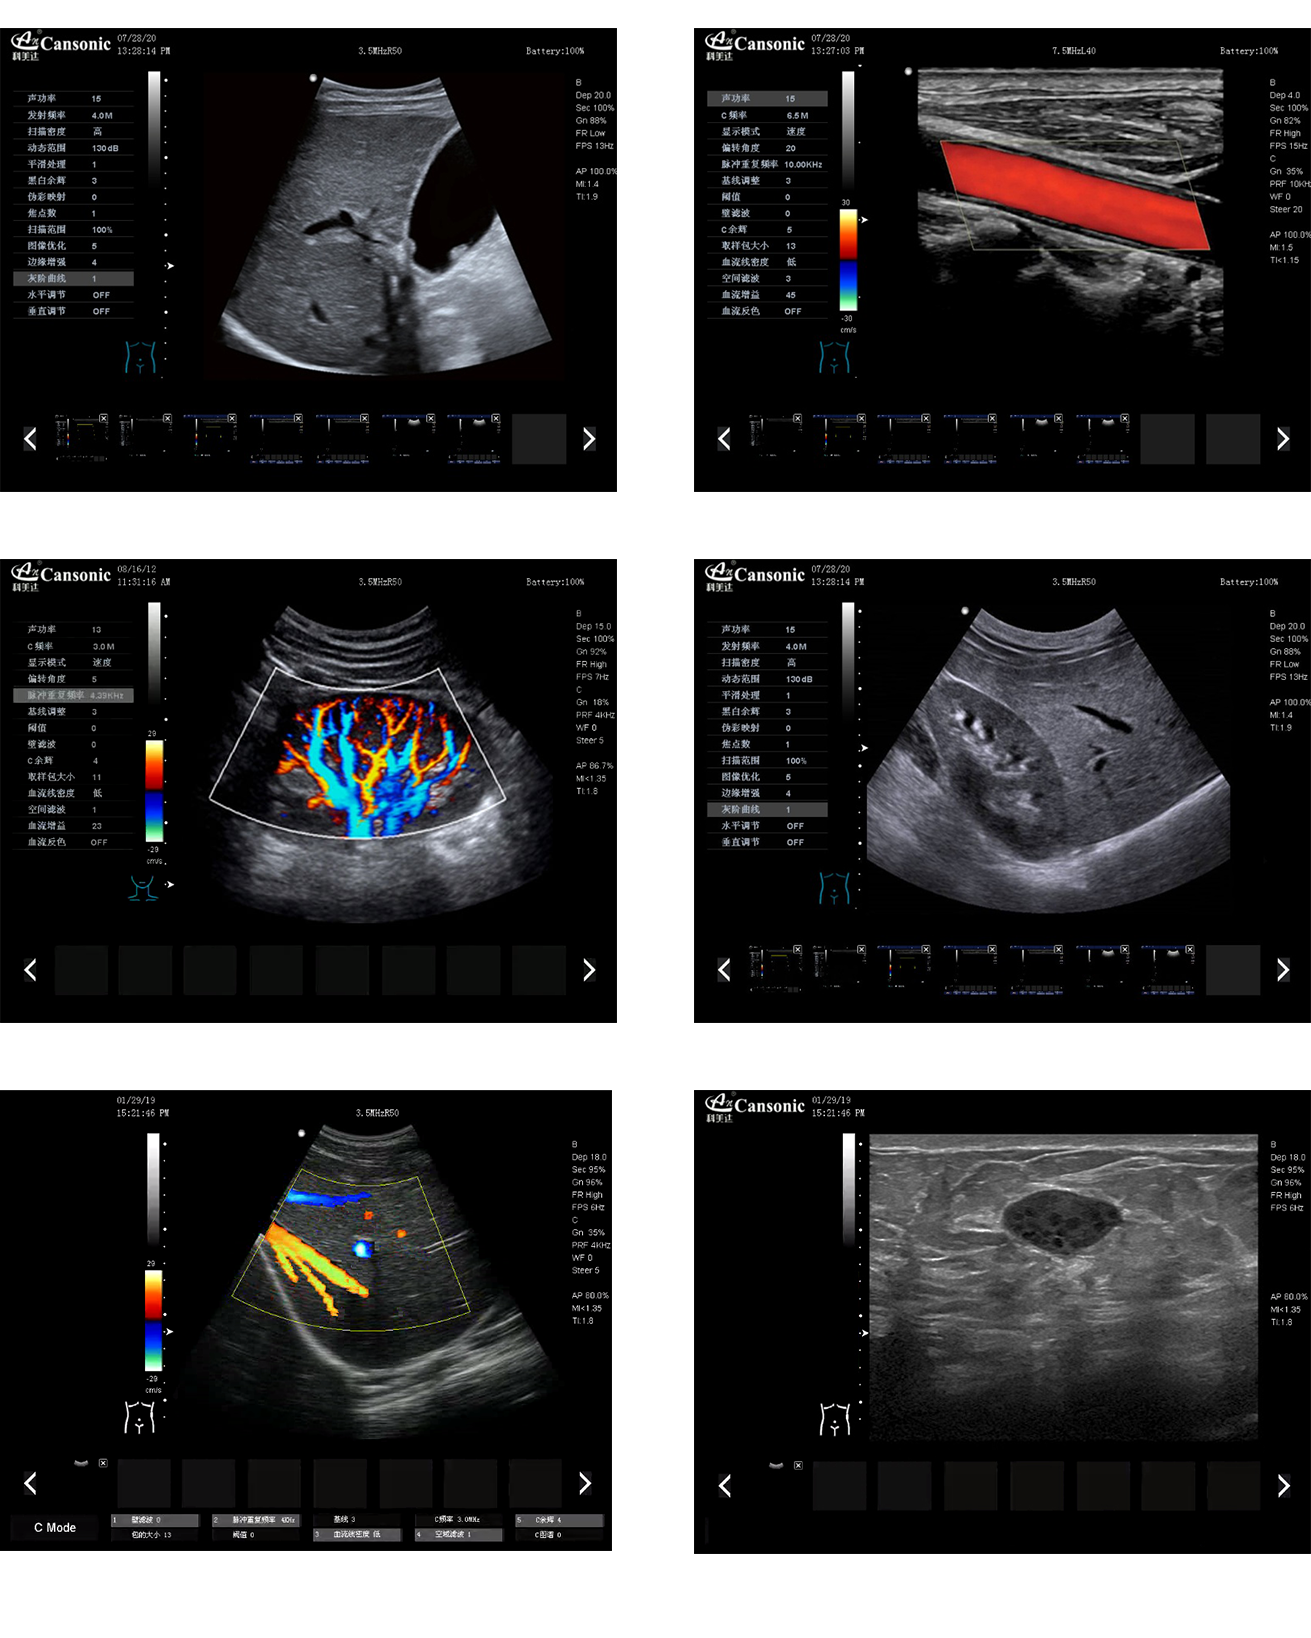

科美達K2圖像實例

1、全身應用型彩超,采用先進的成像技術,具有高清晰度的圖像,擁有完善的臨床應用解決方案

2、圖像質量優異,性能穩定,適合每天的大量診查

3、高幀頻成像技術,多條波束同時處理回波信號,提高了圖像的流暢性

4、自適應斑點消除技術,組織邊界對比度高,圖像細節分辨率優異

5、精準數字濾波技術,有效降低多普勒運動偽像,提升血流靈敏度

6、高分辨率灰階血流成像,明顯提升微細血管的血流探測能力,也利于大血管管壁成像及管壁斑塊的診斷

7、超寬頻帶波束形成和信號處理技術,適用于不同體型的患者掃查